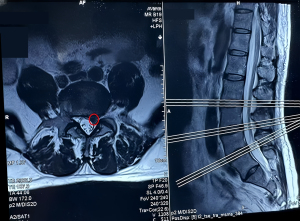

After analysis, we judged that the patient’s symptoms were caused by edema of the L4–L5 left nerve root. Therefore, we decided to perform ultrasound-guided needle knife releasing of the ligamenta flava once every 7 to 10 days. After four treatments, the patient was examined, with the findings being as follows: negative sign on Kernig’s test; a marked decrease in the numbness and pain in the lumbar and leg regions, with the pain no longer affecting normal life; and a VAS score of 3. We also used the SF-36 scale to assess the patients’ quality of life (Table 2). MRI confirmed that the morphology of the responsible nerve root had changed significantly before and after the treatment and indicated the disappearance of the spinal canal indentation (Figure 4).